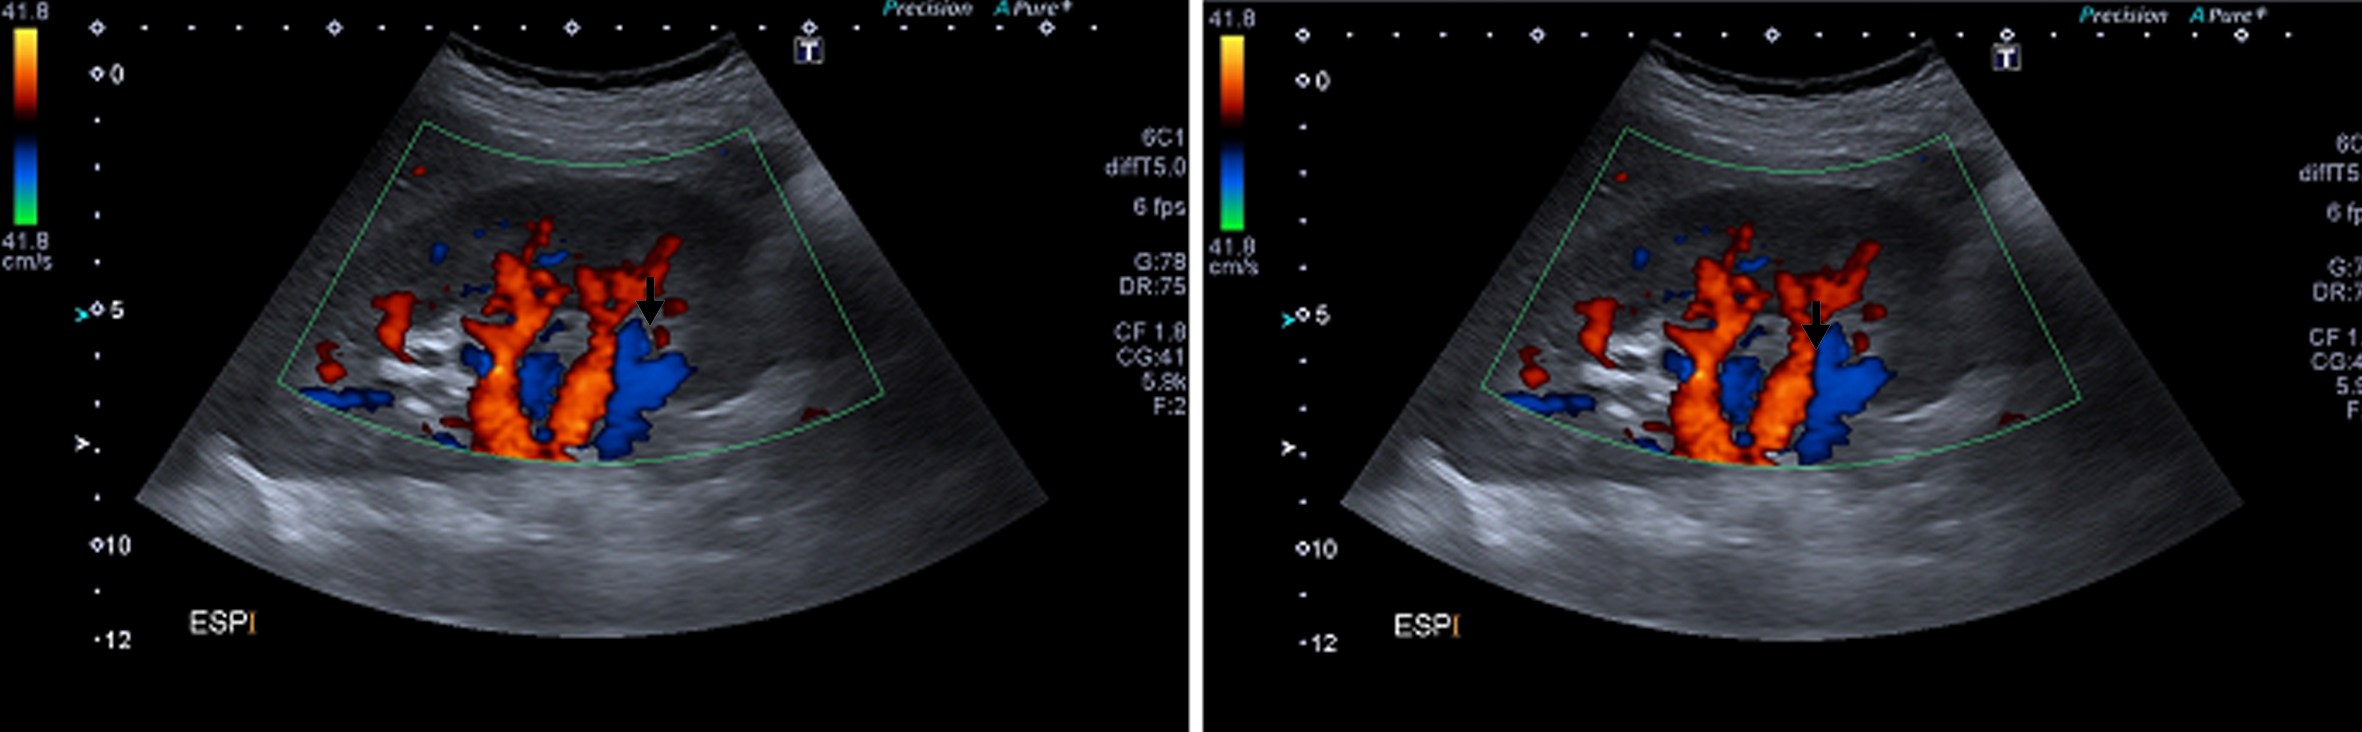

Figura 1

Angiografía de Aorta por TC Cortes axiales. (*) Aorta abdominal, (flecha blanca) Crura diafragmática derecha, (flecha negra) Arteria renal derecha.

La arteria renal derecha es única, se encuentra permeable, y presenta franca disminución de su calibre y trayecto “verticalizado” en su sector proximal, transcurriendo entre la aorta abdominal y la crura diafragmática ipsilateral en su segmento inicial. Distalmente la arteria renal derecha presenta calibre normal, de aprox. 6 mm de diámetro. Así mismo se observa realce asimétrico de ambos riñones tras la administración de medio de contraste i/v, evidenciándose menor captación del mismo en forma difusa a derecha (nefrograma tardío) en comparación con el riñón contralateral, lo cual traduce hipoperfusión renal. (Figs. 1 y 2)

El tronco celíaco y la arteria mesentérica superior se encuentran permeables y de calibre habitual. Se identifica un origen alto de las ramas viscerales de la aorta abdominal, a saber, el tronco celíaco a la altura del espacio discal T11-T12, la arteria mesentérica superior a nivel del cuerpo vertebral de T12, la arteria renal derecha a nivel del espacio T12-L1 y de la arteria renal izquierda a nivel del margen superior de cuerpo de L1. (Fig. 3)